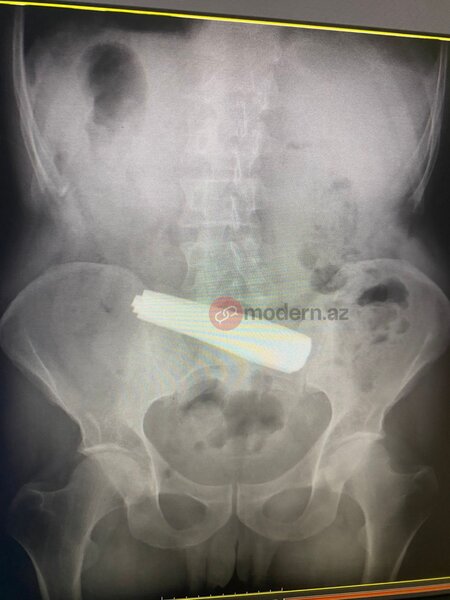

Bakıda bir nəfər 9 ədəd qaşıq uddu (FOTO)

Bakıda bir nəfər 9 ədəd qaşıq udub.

Nəhayət, Bakı Sağlamlıq Mərkəzinə çatdırılan pasiyentə dərhal tibbi müdaxilə olunub. Məlumata görə, xəstə 9 ədəd metal qaşığı udub. Həkimlər tərəfindən həyata keçirilən əməliyyat uğurla başa çatıb.

Hazırda pasiyentin vəziyyəti stabildir və reanimasiya şöbəsində nəzarətdə saxlanılır.